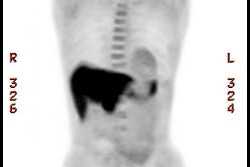

Genitourinary activity: The image below demonstrates normal renal and hepatic activity. |

|